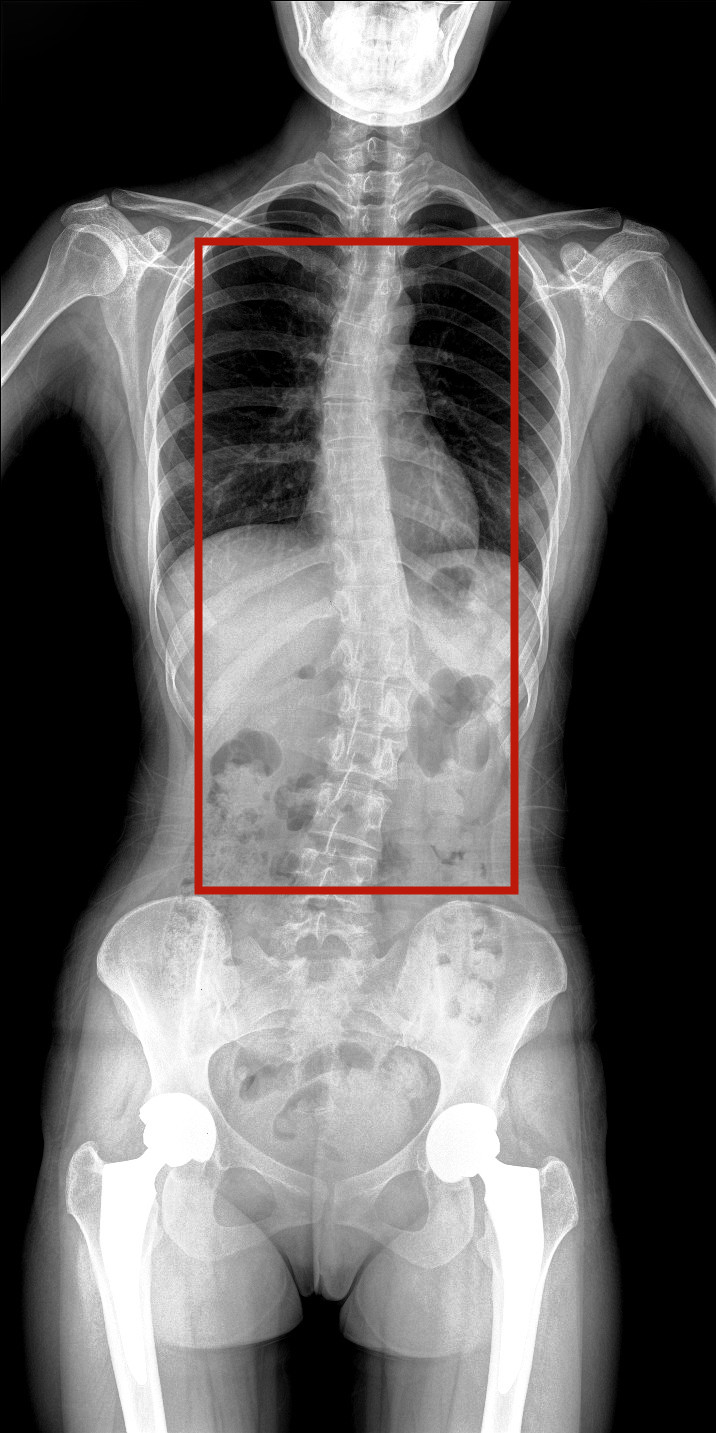

病情描述:患者,女,23歲,免疫系統(tǒng)畸變導致的脊柱側彎

虛線框示患者脊柱側彎明顯

脊柱圖像范圍包含脊椎、雙側肩部及骨盆。片內(nèi)頸椎、胸椎、腰椎、骶椎、雙肩及骨盆重組影像結構清晰,對比度高,對位、對線好,接緣區(qū)無重疊、遺漏、縫隙。能夠滿足臨床測量脊柱Cobb角及臨床人體平衡線等指標的測量,整體上能對全脊柱進行觀察診斷。